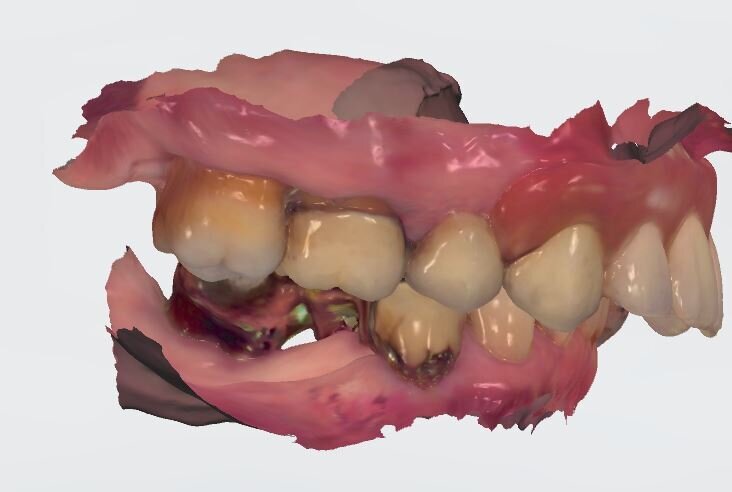

Nell’arcata inferiore dopo il trattamento parodontale abbiamo mantenuto inalterato il V° sestante provvedendo alla rimozione del 3.7 mesio-inclinato con sondaggio e mobilità difficilmente recuperabili e sostituendolo con un impianto. La scelta implantare poco convenzionale ha previsto per la sostituzione bilaterale dei diatorici con impianti in titanio di differente forma e connessione, inserendo bone level (BL) sui premolari e tissue level (TL) sui molari con una protesizzazione mista. La scelta del BL o del TL era rivolta a un aspetto estetico sui premolari e di maggior rispetto tessutale sui molari. Durante le fasi di prova (Fig. 41) si valutano le compressioni dei tragitti transmucosi (Fig. 42), gli eventuali precontatti, si finalizzano le forme e si rileva nuovamente il colore secondo la tecnica di depolarizzazione (Fig. 43).

In laboratorio, l’odontotecnico su nostra indicazione potrà elaborare i file ricevuti, valutando la possibilità di avvitare direttamente il manufatto, solo in caso di forte disparallelismo si opterà per la cementazione. Definita la procedura, verrà realizzato solo il provvisorio su impianti modificando il primo provvisorio che sarà riposizionato dopo il sezionamento dei quadranti (Figg. 27, 28). Dopo il posizionamento del nuovo provvisorio rileviamo una nuova impronta studio (Fig. 29) che analizziamo col software dedicato dello scanner digitale utilizzato.

I dati raccolti sono molti ma la procedura digitale consente di sommarli e confrontarli senza limiti e indicando le possibili migliori e correzioni lungo il percorso. Dopo un breve periodo di condizionamento dei tessuti (Fig. 30) rileviamo l’impronta master per la finalizzazione ultima della riabilitazione protesica. L’impronta degli elementi naturali viene rilevata posizionando dei fili detrattori secondo la tecnica del doppio filo mentre per gli impianti verranno usati gli scan body dedicati (Fig. 31). Le potenzialità digitali consentiranno di avere una stabile lettura della posizione di centrica rilevandola prima della rimozione dei provvisori e sovrapponendola a provvisori rimossi (Fig. 32). In laboratorio l’odontotecnico realizza i modelli (Figg. 33, 34) sovrappone le immagini (Fig. 35) e raccoglie gli elaborati dei vari passaggi che porteranno alla finalizzazione del progetto digitale (Figg. 36, 37).